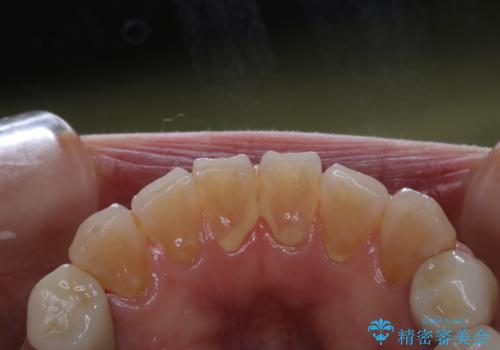

PMTCとはProfessinnal Mechanical Tooth Cleaning・専門器具による歯の機械的な清掃です。

外からは見えない歯周ポケットに汚れが溜まると、歯周病菌が増殖します。歯ブラシが届かない汚れには、歯科でのクリーニングが必要です。

PMTCで、バイオフィルム(細菌の塊)を破壊し、歯の表面をツルツルにすることでお口の中の細菌数を減らし歯周病のリスクが定着するのを防ぎます。更に、歯に新しい汚れがつきにくい状態になります。

バイオフィルムが除去されると、ご自身本来の歯の表面になります。PMTCをすることで口臭予防にもなり、定期的に行うことが大切です。